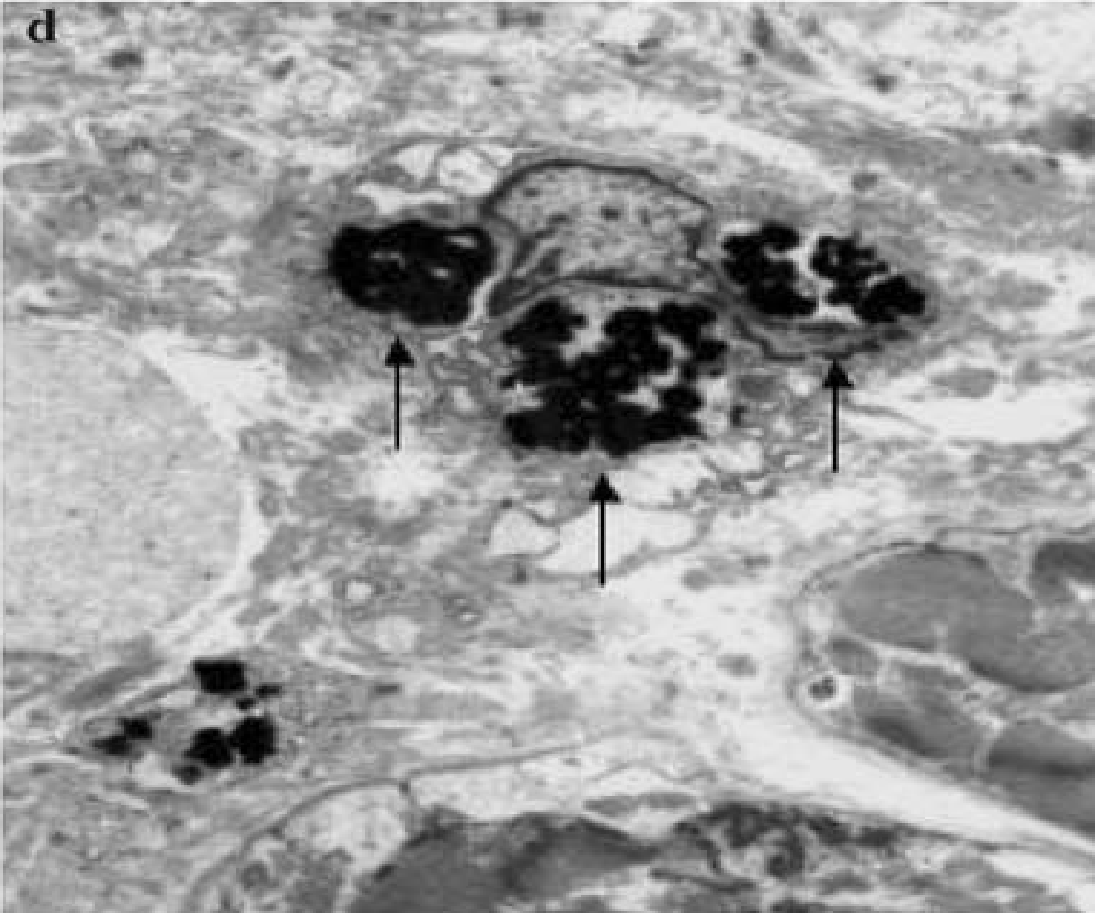

- Фагоцитоз макрофагами апоптотических тел

Поглощение макрофагом апоптотических тел (E.Arbustini и соавторы, 2008)